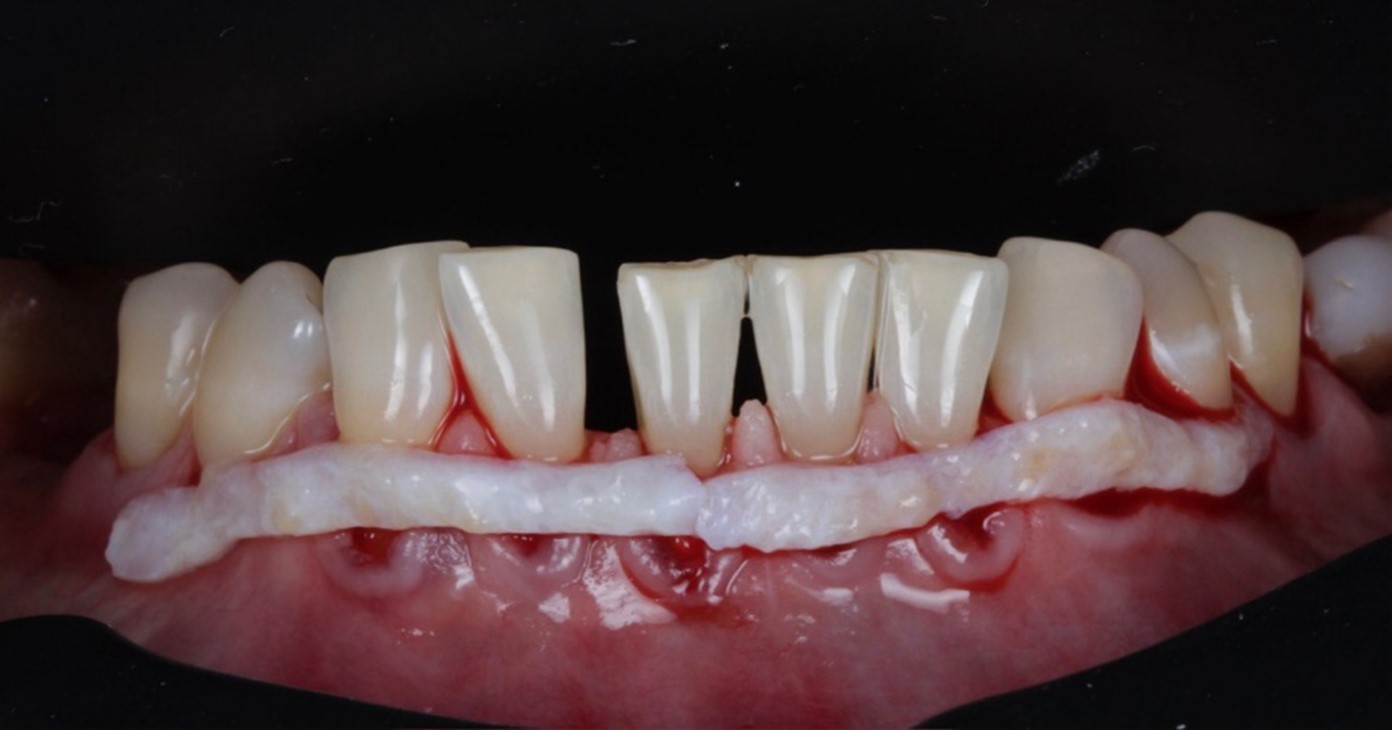

Трансплантаты с нёба — это вот эти белые полосочки

Кроме собственных тканей, можно ещё взять различные коллагеновые мембраны и мембранные матрицы. Мы их используем, если нужен совсем уж большой лоскут. Или если у человека есть какие-то противопоказания к пересадке десны. Например, куча имплантатов и от нёба уже почти ничего не осталось. Но золотой стандарт — это всё-таки пересадка своей слизистой. Она и приживается лучше, и осложнений после такой операции тоже меньше. И долгосрочность результата — выше.